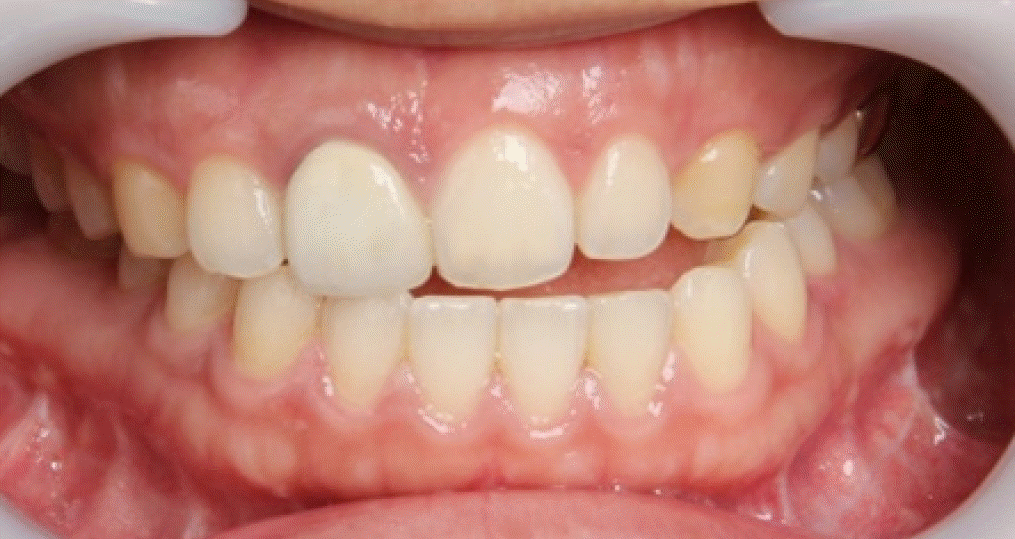

28세 여성이 안면비대칭과 턱관절의 불편감으로 내원하였다. 안모는 우측으로 비대칭이 관찰되었으며, 우측 턱관절부위의 관절잡음이 있었으며 26mm 개구 시 과두걸림이 있었다. 최대개구량은 48mm이고 우측으로 변위된 개구 양상을 보였다. 안면 CT와 X-ray 촬영 결과, 좌측 하악지가 우측 하악지에 비해 12.89mm 길었으며 관절까지의 방향이 우측 하악지에 비해 외측으로 향해 있는 것을 알 수 있었다(Fig. 1). 우측 하악체의 길이가 좌측에 비해 길고 이로 인해 하악 턱끝은 정중선에 비해 우측으로 13.8mm 편위되어 있었다. 그리고 교합평면은 좌측으로 기울어지고 구치부 반대교합과 전치부 절단교합이 존재하였다(Fig. 2). 안면비대칭과 턱관절원판의 정복성 전방변위로 진단하고 하악골의 비대칭과 교합평면의 개선을 위해 턱교정수술과 치아교정술을 계획하였다. 턱교정수술은 상악골 후상방(좌측: 3.5mm, 우측: 4.5mm)이동하고, 하악골은 후방(좌측: 17.5mm, 우측: 5.5mm) 이동하였다(Fig. 3). 턱끝성형술과 하악골 윤곽성형술을 통해 하악골과 안모의 대칭에 도움을 주었다. 하악골수술은 시 시상분할절골술을 이용하였으며, 관절과두가 포함된 근심골편을 재위치시켜주어 과두걸림을 해소하려 하였다. 수술 2주후 치아교정술을 시작하면서 개구연습을 진행하였으며 비대칭적 개구 습관의 교정을 위해 탄성고무줄을 이용하여 중심선에 맞게 진행하였다. 수술 6개월 후 평가 시, 안모의 비대칭은 개선된 결과를 보였으며(Fig. 4) 턱관절 부위의 과두걸림은 관찰되지 않고 정상범위 내의 개구 양상을 보였다.- 증례 2

32세 여성이 우측 턱관절의 통증과 개구제한을 주소로 내원하였다. 내원 전에 3차례에 걸쳐 각각 다른 의료기관에서 턱교정수술을 받은 경험이 있고, 음식물 저작이 힘들고 입이 비뚤어져 사회관계에도 문제가 있었다. 안모는 좌측으로 변위된 비대칭이 관찰되었고 교합은 상악골의 우측 변위, 하악골의 경사진 좌측 변위로 인해 치아 중심선 비대칭을 포함하여 전치부의 개방교합과 구치부의 반대교합이 관찰되었다(Fig. 5). 우측 관절부위 통증과 다수의 수술로 인한 저작근 주위 조직의 경직으로 인해 자발적 최대개구량은 23mm이었다. 파노라마방사선영상에서 우측 하악과두가 좌측에 비해 glenoid fossa으로 부터 떨어져 있고 전방으로 기울어져 있는 것을 관찰할 수 있었다(Fig. 6). 이전 하악골편 고정시 하악과두가 포함된 근심골편이 후방으로 위치하여 고정된 것과 상악골의 우측 변위되어 고정된 것을 개선시키기 위해 4번째 턱교정재수술(4th reoperation)과 치아교정술을 계획하였다. 상악골의 수술 시 하악골의 안정을 위해 후상방이동 2.5mm와 기울어진 교합평면의 개선을 위해 교합평면 수정1.5mm를 하였으며 동시에 상악의 비대칭 개선을 위해 좌측으로 1.5mm 측방이동하였다. 하악골은 기존의 골절선을 이용하여 골편을 분리한 후 변위된 우측 근심골편을 관절와에 재위치시키고 상악골의 위치에 따라 고정하였다. 수술 중 비대칭이 해소된 것과 개구량 45mm 확보된 것을 확인하였다. 수술 후 파노라마방사선영상과 3D CT영상에서 치아의 정중선이 일치하고 전치부 및 구치부의 반대교합이 해소된 것을 볼 수 있었다. 그리고 우측 하악과두가 관절강 내 재위치된 것과 하악지의 방향이 좌, 우측 비슷하다는 것을 확인할 수 있었다(Figs. 7 and 8). 수술 후 2주부터 개구연습과 치아 교정을 진행하였으며, 수술 후 3개월에 자발적 개구량 35mm 확인하였다. 다수의 수술로 인한 구강내 반흔 조직과 저작근 주위의 경결감으로 인해 적극적인 개구훈련을 하였으며 수술 후 6개월에 38mm의 개구량을 보였으나 통증은 없고 일상식이 가능하여 이후의 경과관찰에는 내원하지 않았다.- 증례 3